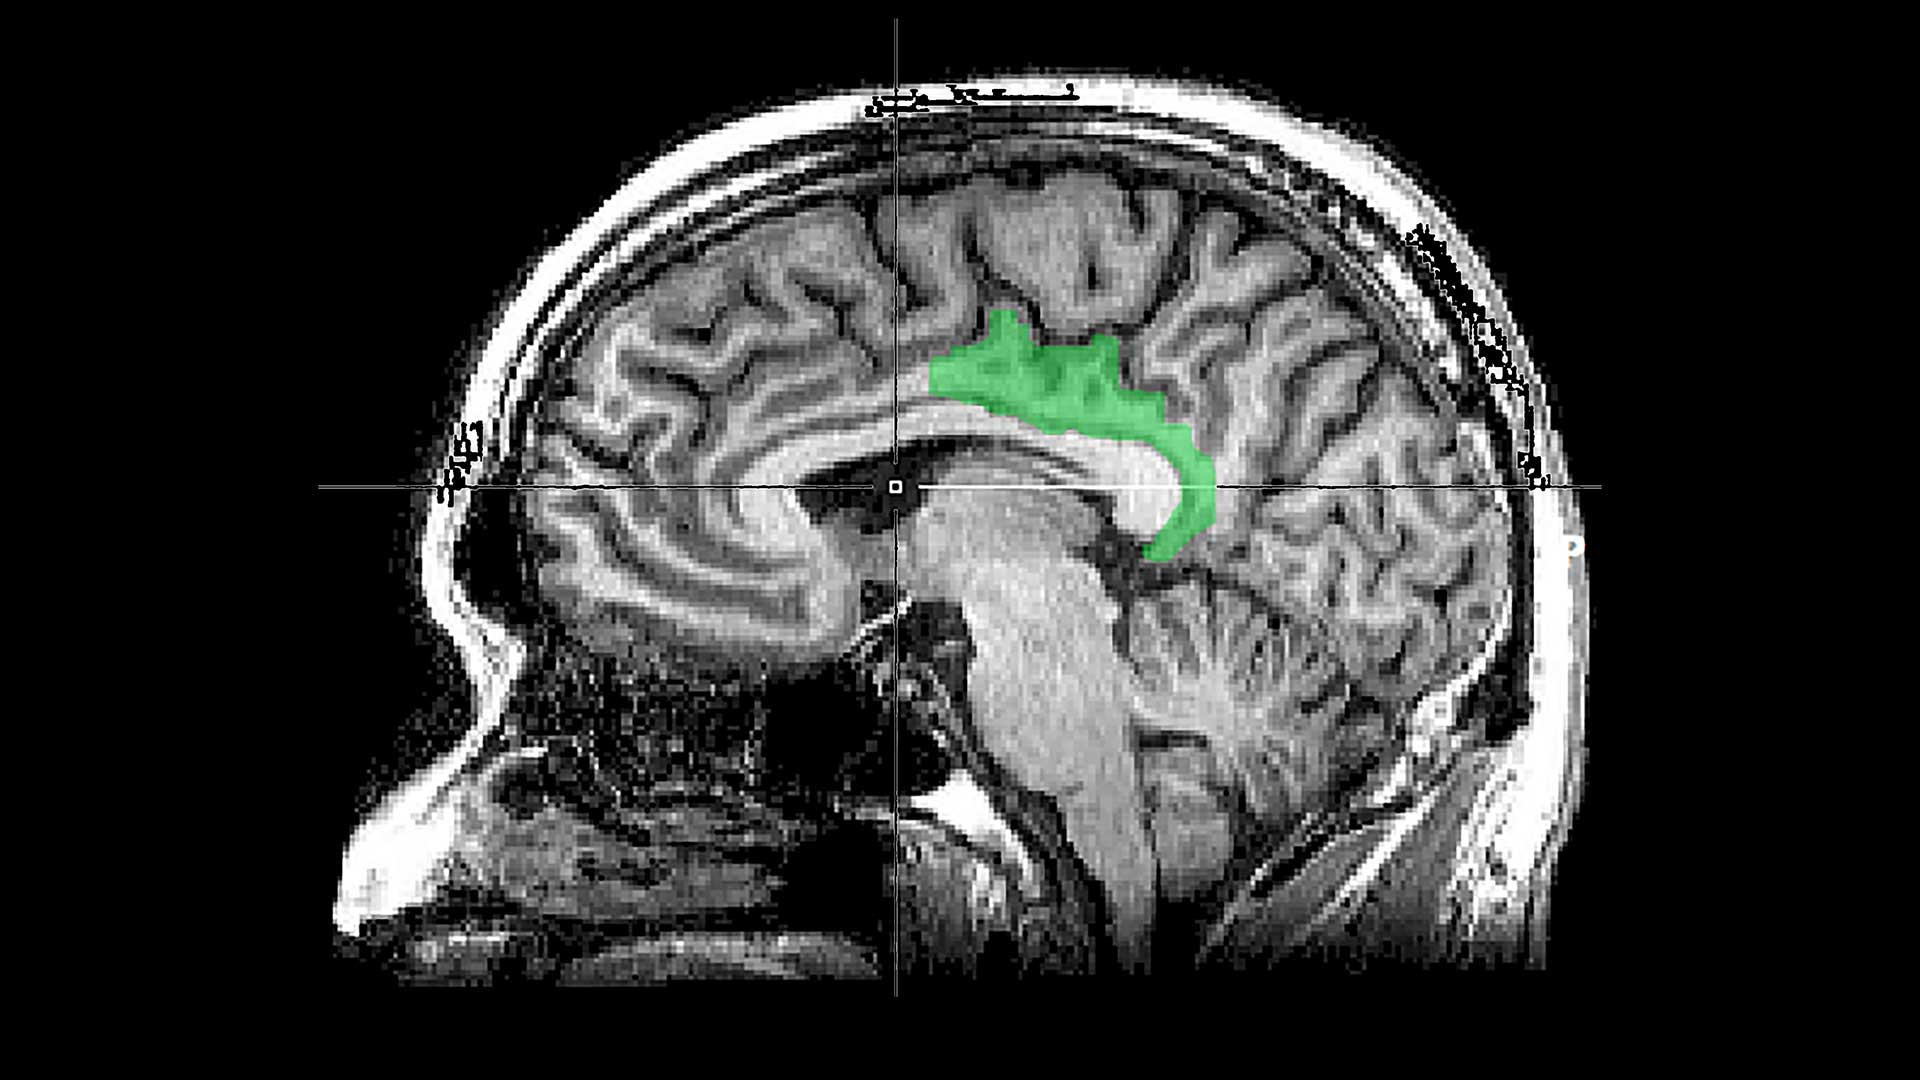

Οι ερευνητές ανέφεραν σε άρθρο που δημοσιεύθηκε πριν μερικές μέρες στο περιοδικό Nature Neuroscience ότι οι εγκεφαλικές σαρώσεις σημείωσαν ξεκάθαρες διαφορές ανάμεσα στα είδη των αναμνήσεων. Αυτοί που άκουγαν τις «θλιμμένες» αναμνήσεις, οι οποίες συχνά αφορούσαν τον θάνατο ενός μέλους της οικογένειας, παρουσίασαν σταθερά έντονη λειτουργία του ιππόκαμπου, του τμήματος του εγκεφάλου που οργανώνει και πλαισιώνει τις αναμνήσεις.

Όταν οι ίδιοι άνθρωποι άκουγαν τις τραυματικές αναμνήσεις τους – από σεξουαλικές επιθέσεις, πυρκαγιές, πυροβολισμούς σε σχολεία και τρομοκρατικές επιθέσεις – ο ιππόκαμπος δεν συμμετείχε.

Οι τραυματικές αναμνήσεις φάνηκε να εμπλέκουν μια διαφορετική περιοχή του εγκεφάλου: τον οπίσθιο φλοιό του προσαγωγίου, ο οποίος συνήθως εμπλέκεται στην εσωτερικευμένη σκέψη, όπως την ενδοσκόπηση ή την ονειροπόληση. Όσο πιο σοβαρά ήταν τα συμπτώματα μετατραυματικού στρες του ασθενή, τόσο πιο έντονη δραστηριότητα εμφανιζόταν στον οπίσθιο φλοιό του προσαγωγίου.

Το εντυπωσιακό σε αυτό το εύρημα είναι ότι ο οπίσθιος φλοιός του προσαγωγίου δεν είναι γνωστός ως ένα τμήμα του εγκεφάλου που σχετίζεται με τη μνήμη, αλλά ένα τμήμα που ασχολείται με την «επεξεργασία της εσωτερικής εμπειρίας», δήλωσε η Σίλερ.